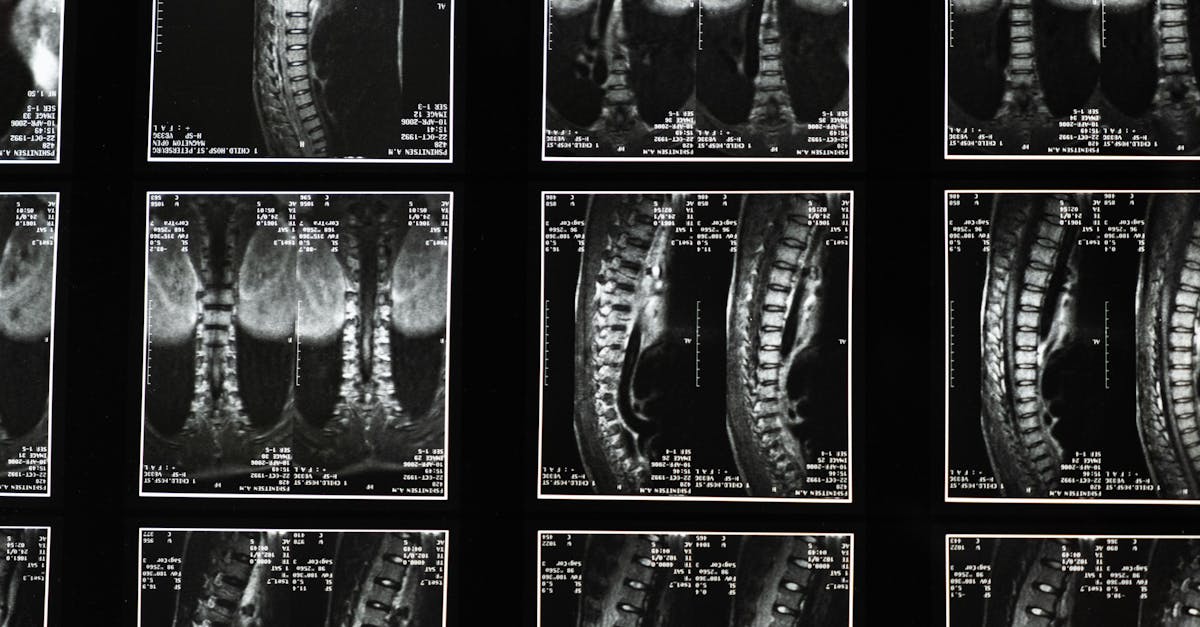

La décompression neurovertébrale se présente comme une approche efficace pour soulager les douleurs chroniques localisées, notamment celles liées aux hernies discales, aux bombements discaux et aux pincements discaux. Ce traitement cible les racines nerveuses et les disques intervertébraux afin de réduire la pression, favorisant ainsi la régénération des tissus et le soulagement des douleurs. Dans cet article, nous explorerons les avantages de cette méthode et son fonctionnement pour les patients.

La décompression neurovertébrale est une thérapeutique manuelle qui vise à réduire la pression sur les disques intervertébraux. À travers des manipulations spécifiques, elle améliore la circulation sanguine et augmente l’apport de nutriments aux zones affectées. Cela favorise la guérison et le soulagement de la douleur.

Une séance de décompression neurovertébrale commence généralement par une évaluation approfondie des symptômes du patient. Ensuite, le praticien utilise des techniques manuelles pour appliquer une pression contrôlée sur la colonne vertébrale, permettant ainsi de créer un espace entre les vertèbres. Cette manipulation est non invasive et se fait en douceur.

La décompression neurovertébrale est une méthode non invasive qui consiste à créer un espace entre les vertèbres pour réduire la pression sur les nerfs et les disques. Ce processus peut être réalisé à l’aide d’appareils spécifiques ou par des techniques manuelles dont l’objectif est d’étirer délicatement la colonne vertébrale. Cela permet d’améliorer la circulation sanguine et l’apport de nutriments, favorisant ainsi la guérison des tissus et atténuant la douleur.

La décompression neurovertébrale repose sur des principes fondamentaux d’ostéopathie et de médecine manuelle, offrant ainsi un soin adapté à chaque individu. En utilisant des appareils spécialement conçus, les praticiens appliquent une traction douce sur la colonne vertébrale, permettant ainsi de créer un espace entre les vertèbres. Ce procédé aide à la réduction de la pression sur les disques intervertébraux, favorisant leur régénération et la réduction des inflammations. Les patients, souvent confrontés à des douleurs récurrentes, découvrent un soulagement significatif après quelques séances de traitement.